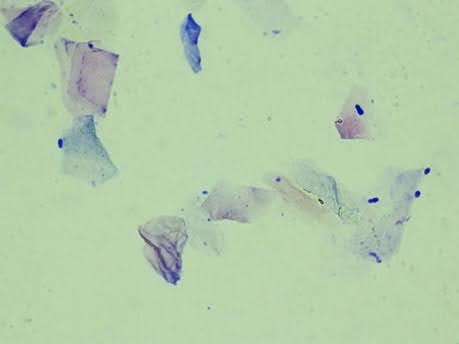

Les éléments visibles à l’examen cytologique sont faciles à décrypter :

Crédit photo : Dr. Vet E. Bensignor

Il faut idéalement prélever dans les portions verticale et horizontale du conduit (en tirant le pavillon vers l’arrière pour passer facilement l’écouvillon). Les prélèvements seront de préférence faits en utilisant les bâtonnets fournis par les centrales : il faut qu’ils soient de grande taille et que le coton ne se délite pas à l’intérieur du conduit. Lorsque le temps manque pour faire une coloration complète, le simple passage au bleu de méthylène peut suffire pour visualiser les bactéries, les granulocytes et les Malassezia.